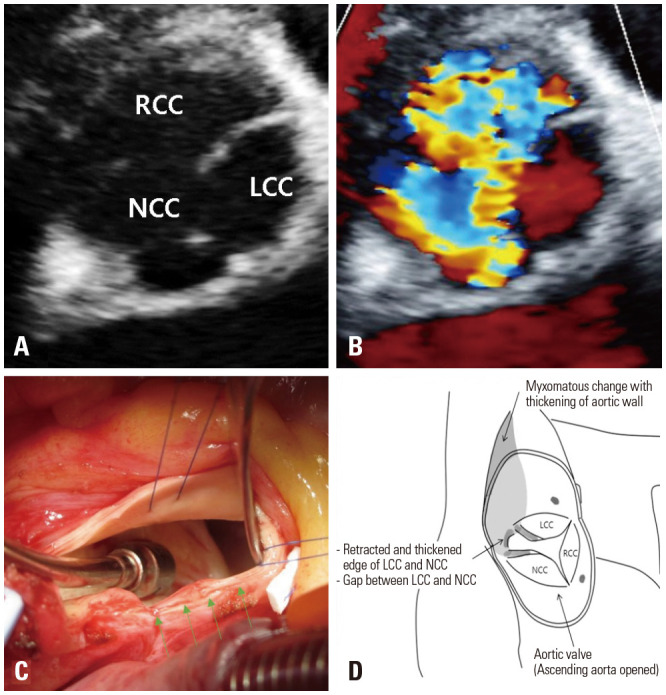

Aortic regurgitation (AR) in children is usually caused by congenital valve anomalies, and Behçet syndrome (BS) can be suspected in cases of isolated AR. Patients with BS undergoing aortic valve surgery due to aortic valve invasion have a high risk of complications, such as leakage around the valve and dehiscence. Cardiovascular involvement occurs in 7%-46% of adult patients with BS and is the main cause of mortality; however, its prevalence is unclear and rare in children. A 12-year-old boy was diagnosed with severe AR associated with BS. A progressive subaortic pseudoaneurysm was observed after aortic valve replacement. The periaortic intracardiac pouch was at risk of rupture; therefore, the patient underwent a Bentall operation. After the Bentall procedure, a newly developed subaortic pseudoaneurysm was detected below the prosthetic valve. However, the risk of rupture reduced as the subaortic pseudoaneurysm regressed with anti-inflammatory drugs alone without reoperation. Repeated surgery is inevitable in patients with BS undergoing aortic valve surgery due to the progressive chronic inflammatory reactions that present with a pseudoaneurysm. Here, we report an 8-year follow-up of a pediatric case of BS with subaortic pseudoaneurysm, highlighting the importance of close follow-up, medical management, and early diagnosis in treating this condition.

Abstract Image